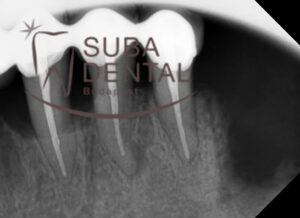

Intraoral radiograph of bone resorption around the teeth with periodontal pockets and inflammation